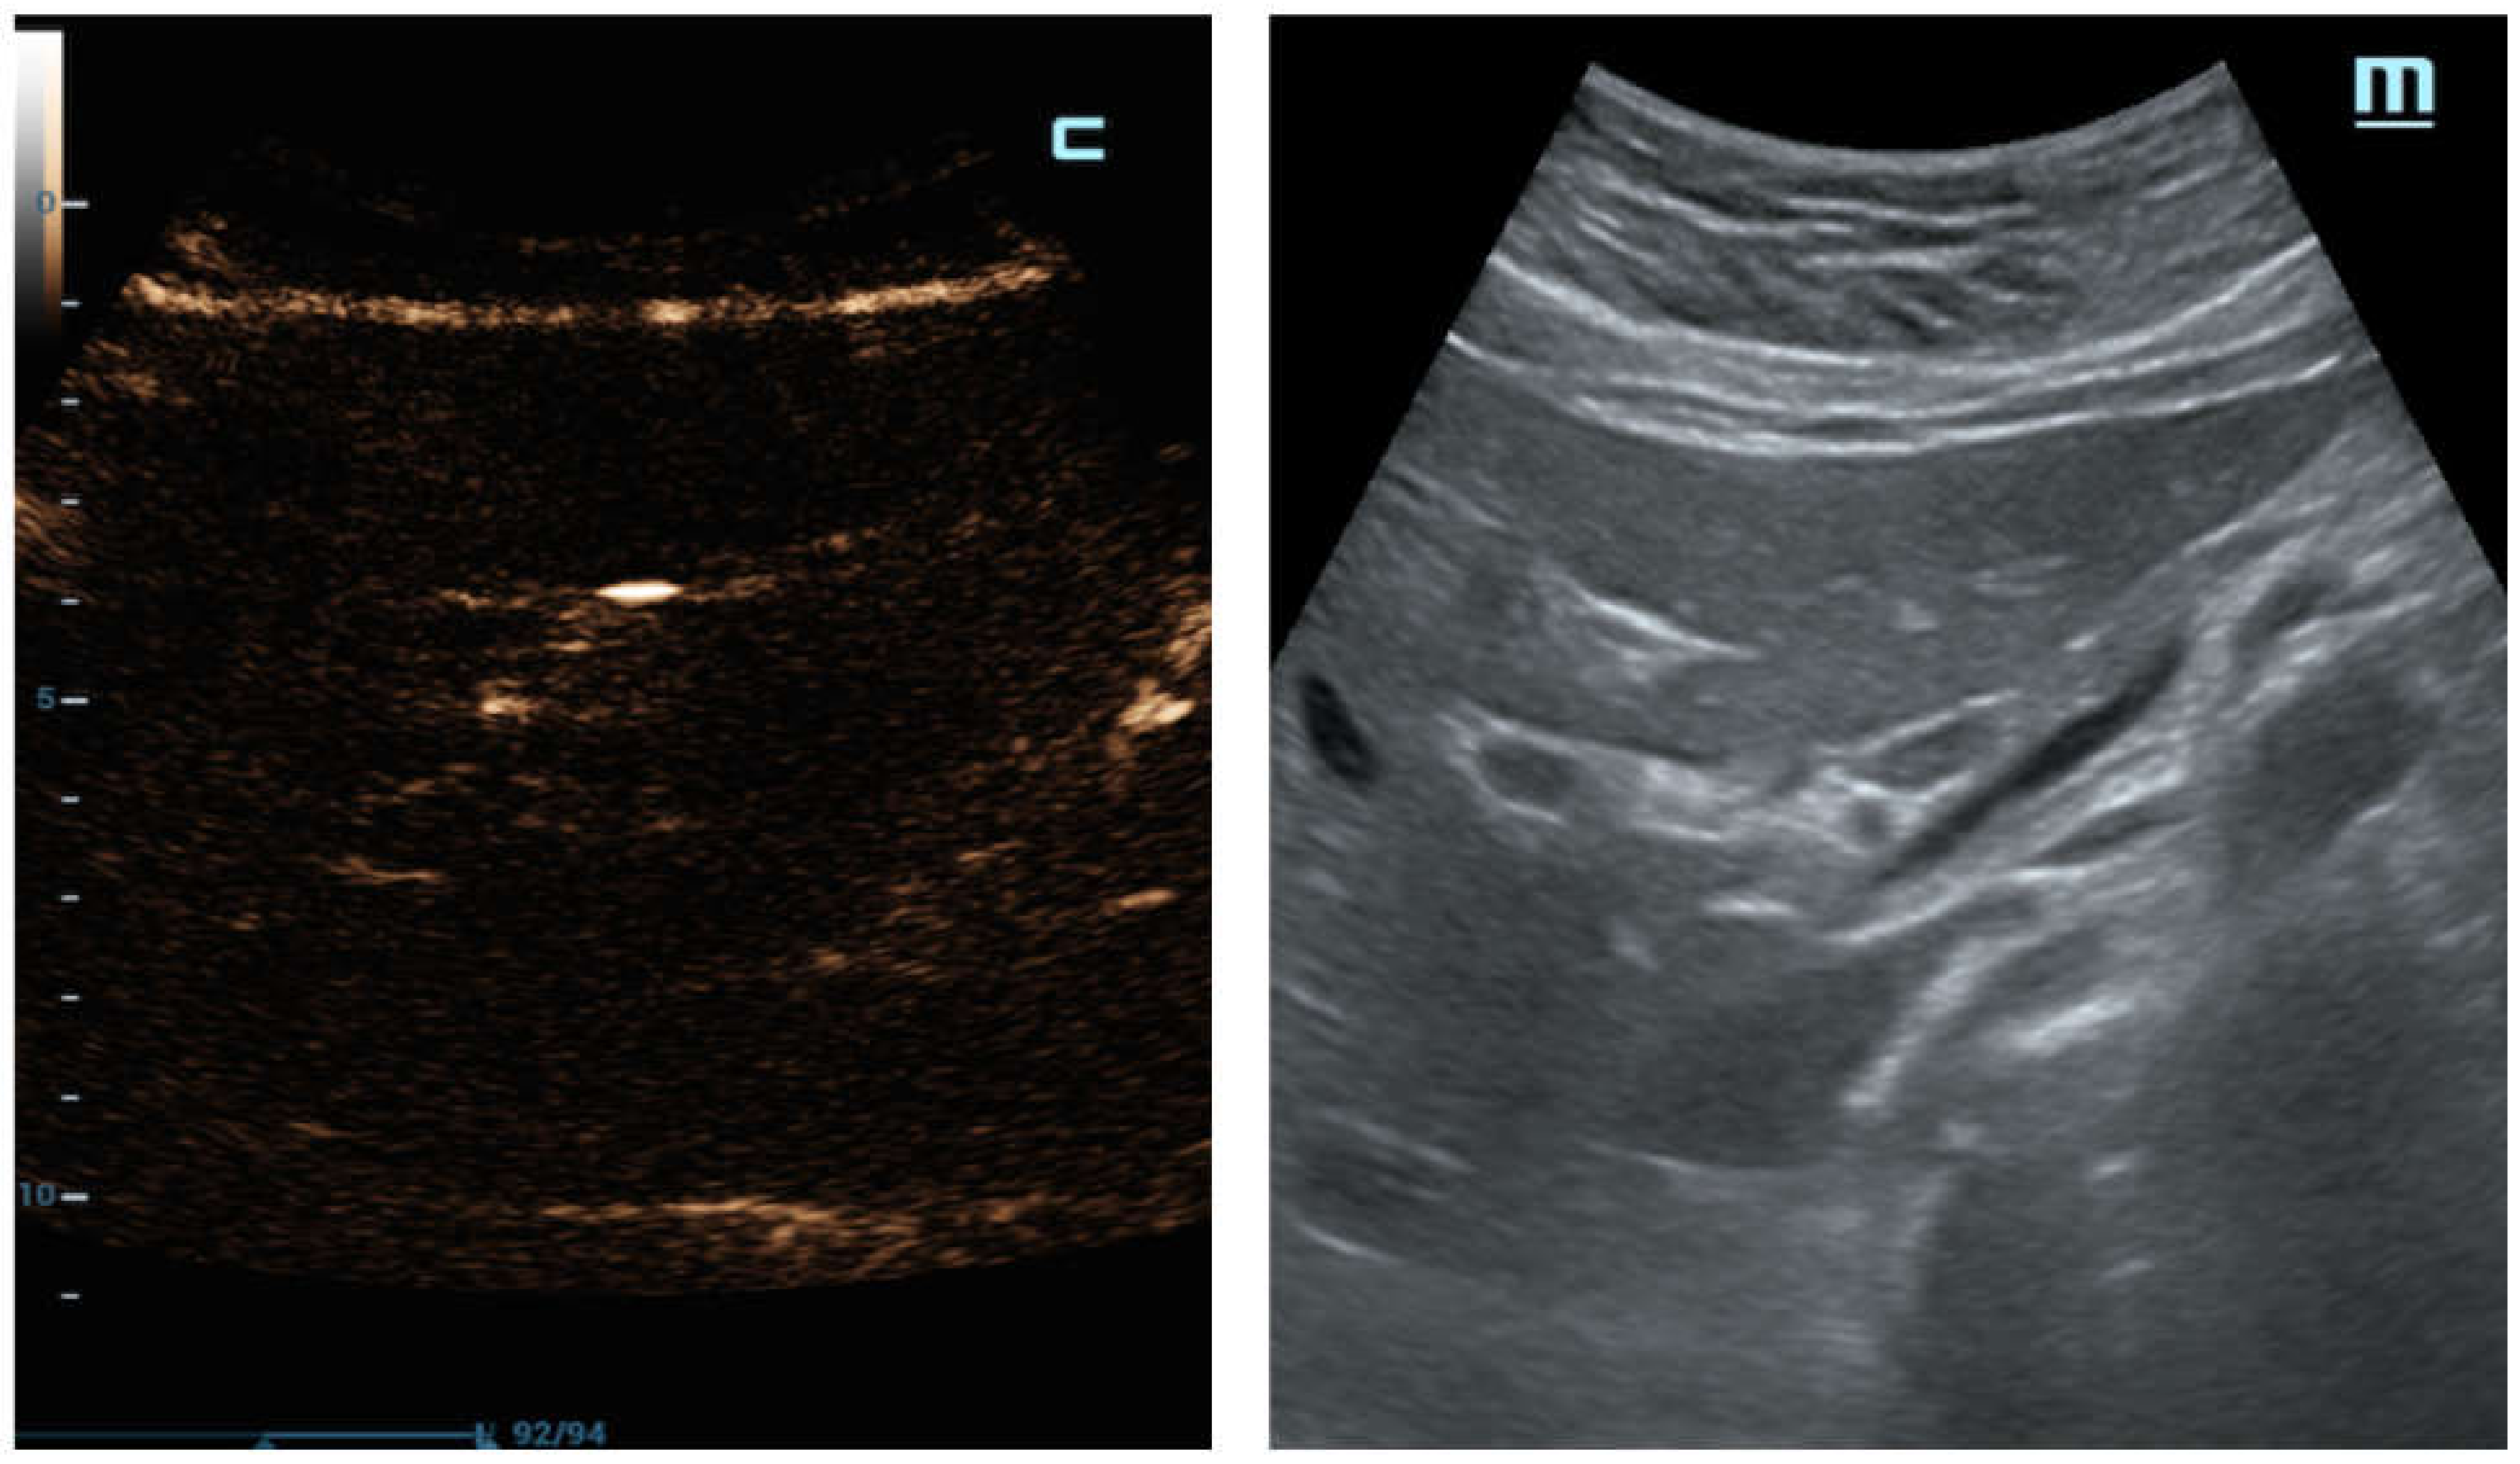

In another case, C-mode was able to detect free abdominal air around the duodenum and the pancreatic head with certainty (

Figure 6a), which was also displayed perfectly by the CT scan (

Figure 6b).

As observed in

Figure 7, an accurate B-mode examination could also lose a minimal amount of free gas; the same patient was correctly detected on C-mode, discriminating a few air bubbles as bright punctuate foci of the luminescent echo line.